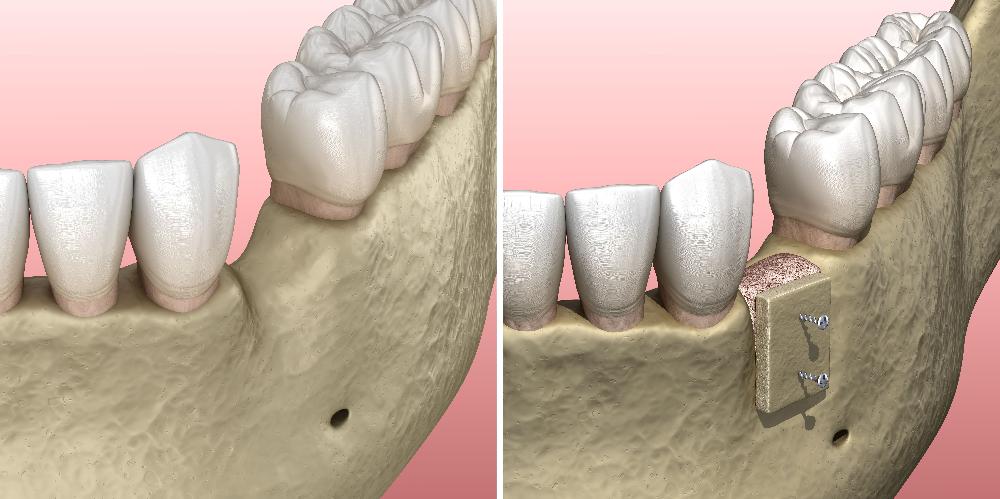

Bone Grafting

Bone grafting is an essential procedure often performed in conjunction with dental implant planning. When the natural bone volume is insufficient, bone grafting is incorporated to address the deficiency. At ICS Dental Studio, Dr Skaf utilises bone grafting techniques to rebuild and augment the jawbone, providing a solid foundation for successful dental implant placement. This procedure is planned carefully to ensure optimal results and long-term implant stability. Bone grafting is necessary when there is insufficient bone volume, preserving the jawbone and enhancing the overall success of dental implant treatments.

During the bone grafting procedure at our East Hills dental practice, a small incision is made in the gum tissue to access the underlying bone. Then, bone graft material, which can be synthetic, from a donor or taken from the patient’s own body, is placed in the deficient area. The graft material serves as a scaffold, providing support and stimulating the natural growth of new bone cells. Over time, the grafted bone integrates with the patient’s existing bone, creating a stronger and healthier foundation for dental implants or other restorative treatments.

After the bone grafting procedure, a healing period is necessary for the new bone to develop and mature. This can take several months; during this time, the patient’s oral health and hygiene should be carefully maintained. Following successful bone grafting, patients can proceed with dental implant placement or other necessary dental procedures, restoring function and aesthetics to their smiles.